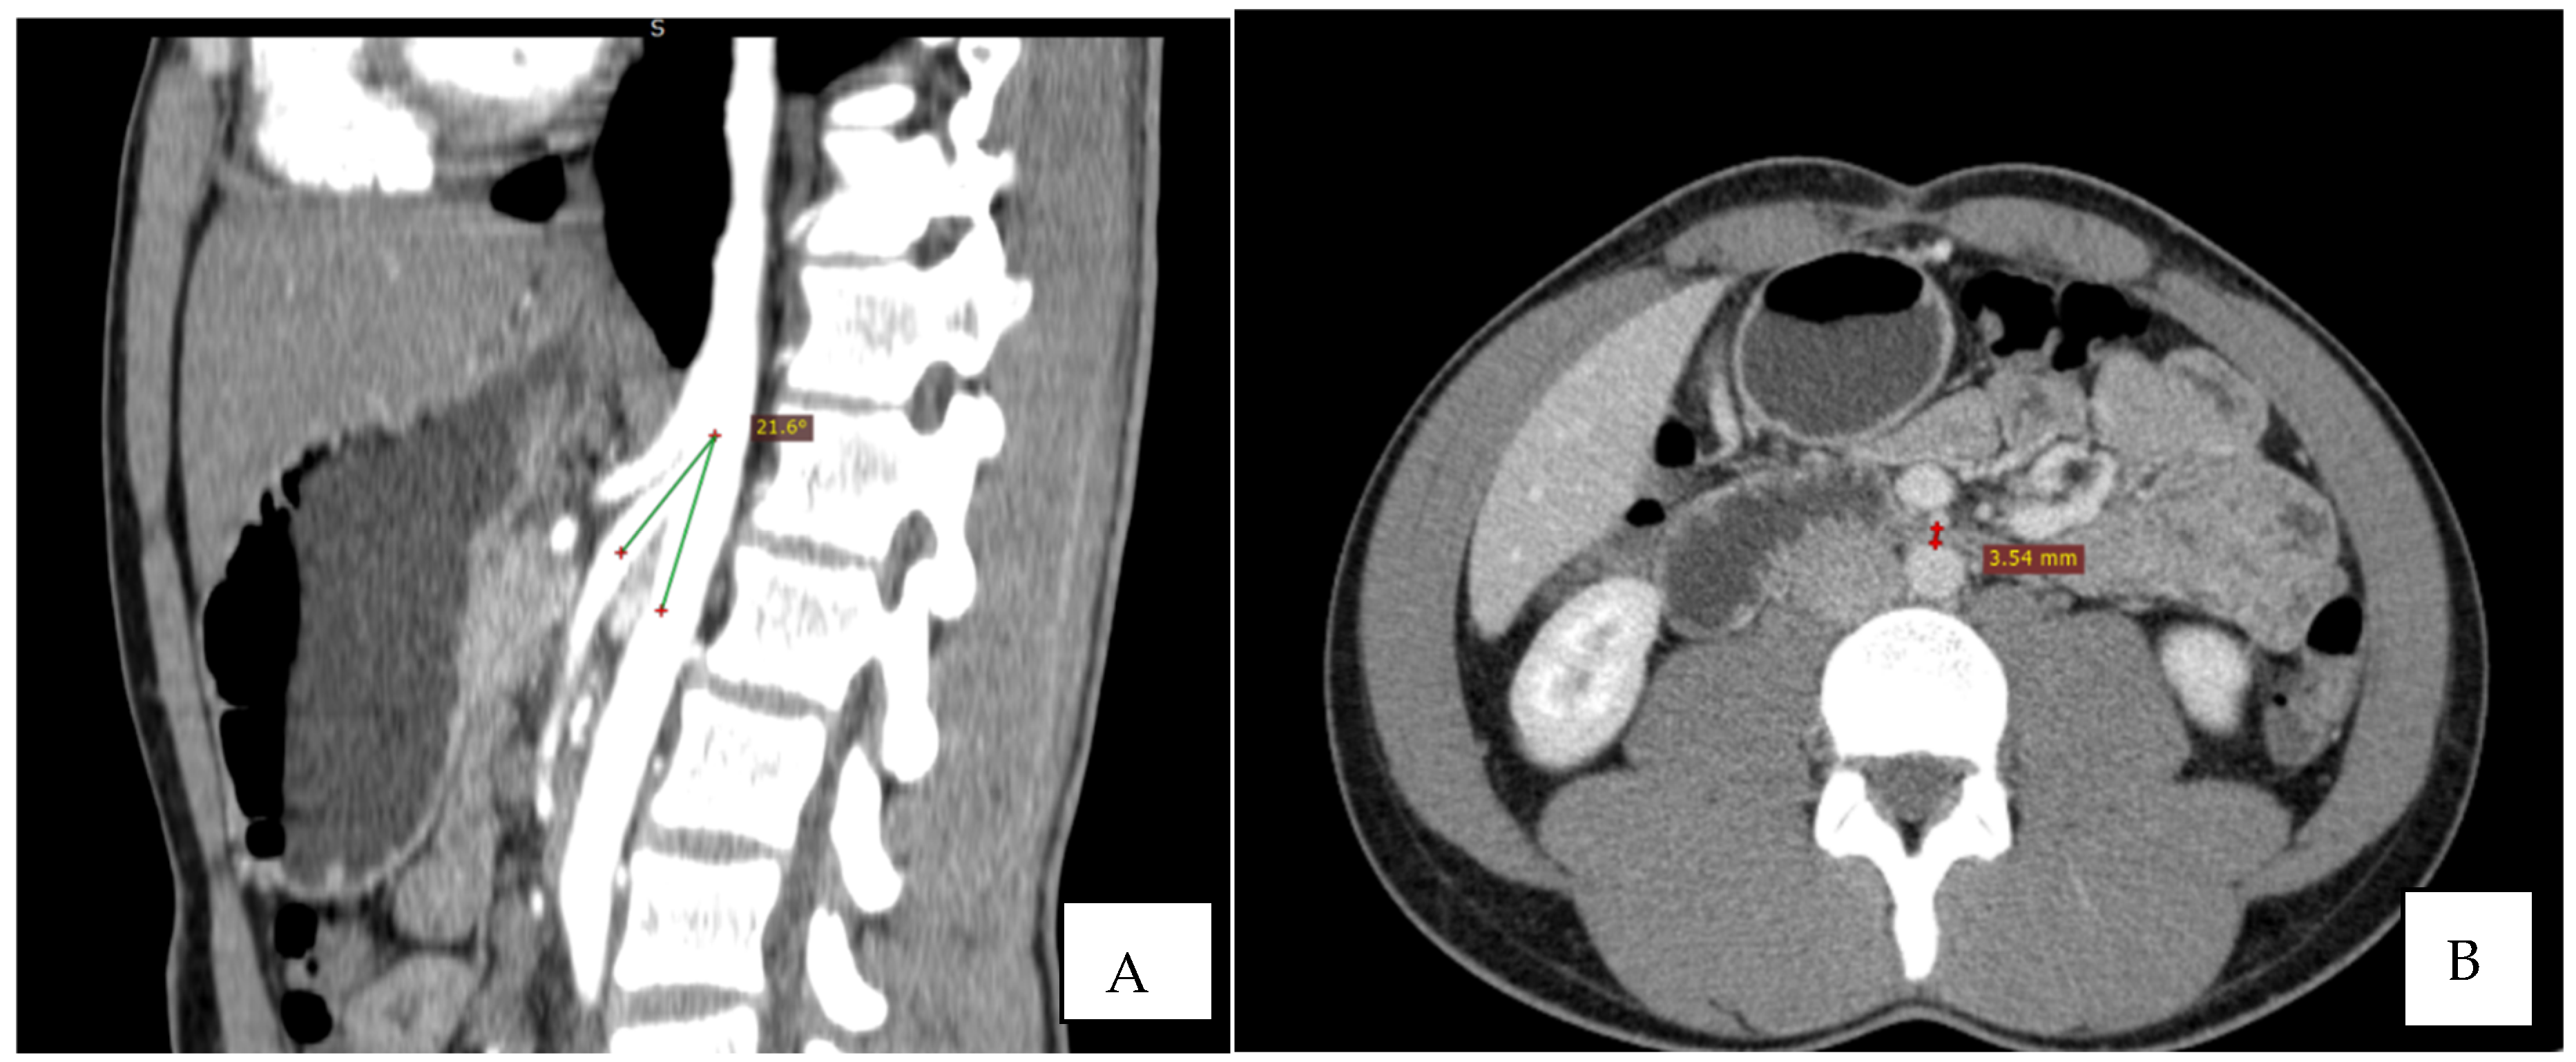

Immediate exploration of the abdomen was performed in the Emergency Department using X-rays, ultrasound, and a computed tomography (CT) scan of the abdomen. The abdominal ultrasound revealed an enlarged stomach (Figure 2), and the CT showed a vascular abnormality with a reduction of the aorto-mesenteric space of 21.6° and a distance (3.54 mm) obstructing the third portion of the duodenum, and partial left renal vein stenosis confirming the diagnosis of SMAS and Nutcracker syndrome (Figure 3).

Figure 3.

CT: the sagittal reconstruction shows the reduction of aorto-mesenteric angle. ((A) beak signand distance (B)).

As previously mentioned, the third portion of the duodenum is positioned at the angle formed by the aorta and the superior mesenteric artery. A narrow-angle would enable the obstruction of the third segment by the arterial vessels due to a loss of retroperitoneal and mesenteric fat deposits which are surrounding the vascular structures [4,14]. The normal angle between the aorta and the superior mesenteric artery (measured on the mid-sagittal image between the abdominal aorta and mesenteric artery) is considered to be from 25–65° [15]. In patients with SMAS, the angle is reduced below 25° [16]. Equally important is the aorto-mesenteric distance (measured on the axial image at the level of the horizontal third part of the duodenum between the abdominal aorta and mesenteric artery) which is also reduced from a normal range of 10–28 mm to below 10 mm in SMAS [15]. Furthermore, left renal vein compression may also be present and patients may be completely asymptomatic or might develop symptoms such as hematuria, varicocele, pain in the left flank, or even renal vein thrombosis, a syndrome called Nutcracker syndrome [17]. The association of both syndromes is a common occurrence. Nutcracker syndrome, also known as left renal vein entrapment, is characterized by an impaired venous outflow from the left renal vein into the inferior vena cava due to extrinsic compression, often accompanied by obvious dilatation and narrowing [8,17]. The lack of retroperitoneal fat which can reduce the aortomesenteric angle, causing vascular compression, is the main culprit. The syndrome may imply compression of the vein between the aorta and the SMA, or in other cases the retro aortic renal vein may be compressed between the aorta and the vertebral body, causing the posterior nutcracker syndrome [8]. Hematuria and pain are the most common symptoms described by patients. Hematuria is attributed to the rupture of small vessels due to elevated venous pressure, in the collecting system [15,17]. It varies from microhematuria to macrohematuria and can be associated with anemia. Flank or posteromedial thigh pain may be triggered when walking, sitting, or standing explained by the passing of blood clots [17].